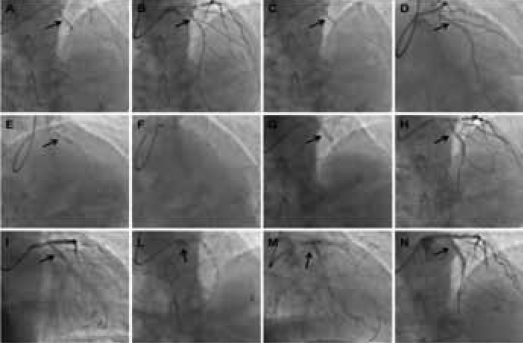

诊断为冠心病、不稳定性心绞痛。择期行冠脉造影示:LAD近段90%,LAD中段 75%,D1和D2分别为90%50% 狭窄LAD可见较明显钙化(图1A)。LCX近段90%、OM1和OM2均为90% 狭窄,伴明显钙化(图1A);RCA段PL为40% 狭窄。告知患者冠脉严重病变伴钙化、老龄、患者心脏功能差、手术风险高,但家属拒绝CABG,决定行冠脉PCI 术。

患者年龄大,血管病变严重伴钙化较重的情况下,行预旋磨可节省时间间,降低造影剂用量,减少并发症发生,因此首先行预旋磨术。此病例旋磨过程:(1)选用强支撑指引导管EBU3.5(图1A);(2)Runthrough NS 导丝+微导管送到LAD 远端,换为旋磨导丝;(3)左冠血管狭窄重,直径小,旋磨小磨头1.25 mm,18 万转/分,20 s,共旋磨4 次(图1B)。旋磨过程中助手密切注意心率、血压变化,如心率、血压下降至90/60 mmHg 后立即停旋磨,如心率下降明显,给予阿托品和多巴胺或肾上腺素。此患者心率血压略下降,旋磨造影血流改善(图1C);(4)LCX与主干夹角约≥70°,旋磨LCX 时指引导管略提起,使两者夹角变小,避免旋磨头嵌顿(图1D);磨头1.25mm,18 万转/ 分,20 s,共旋磨3次;(5)LCX 旋磨图1左冠脉旋磨过程图2左冠脉球囊扩张和支架过程后腔隙增大,导丝不易进入前降支,多次尝试后进入LAD(图1E);(6)再次造影左冠血流改善(图1F)。

图1 左冠脉旋磨过程图